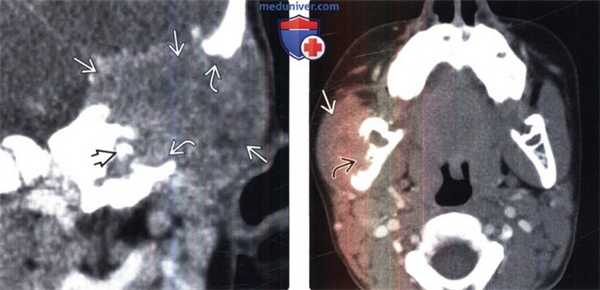

(Слева) КТ с контрастированием, корональный срез: у пятилетнего мальчика с хронической левосторонней отореей и кондуктивной тугоухостью определяется мягкотканное объемное образование в сочетании с деструкцией сосцевидного отростка теменной кости. Обратите внимание на четкие контуры дефекта кости и смещение слуховой косточки.

(Справа) КТ с контрастированием, аксиальный срез: у ребенка с медленно растущим объемным образованием в области правой щеки визуализируется объемное образование в виде мягкотканного компонента, расположенного в нижних отделах жевательного пространства. Обратите внимание на лизис наружных отделов ветви нижней челюсти.